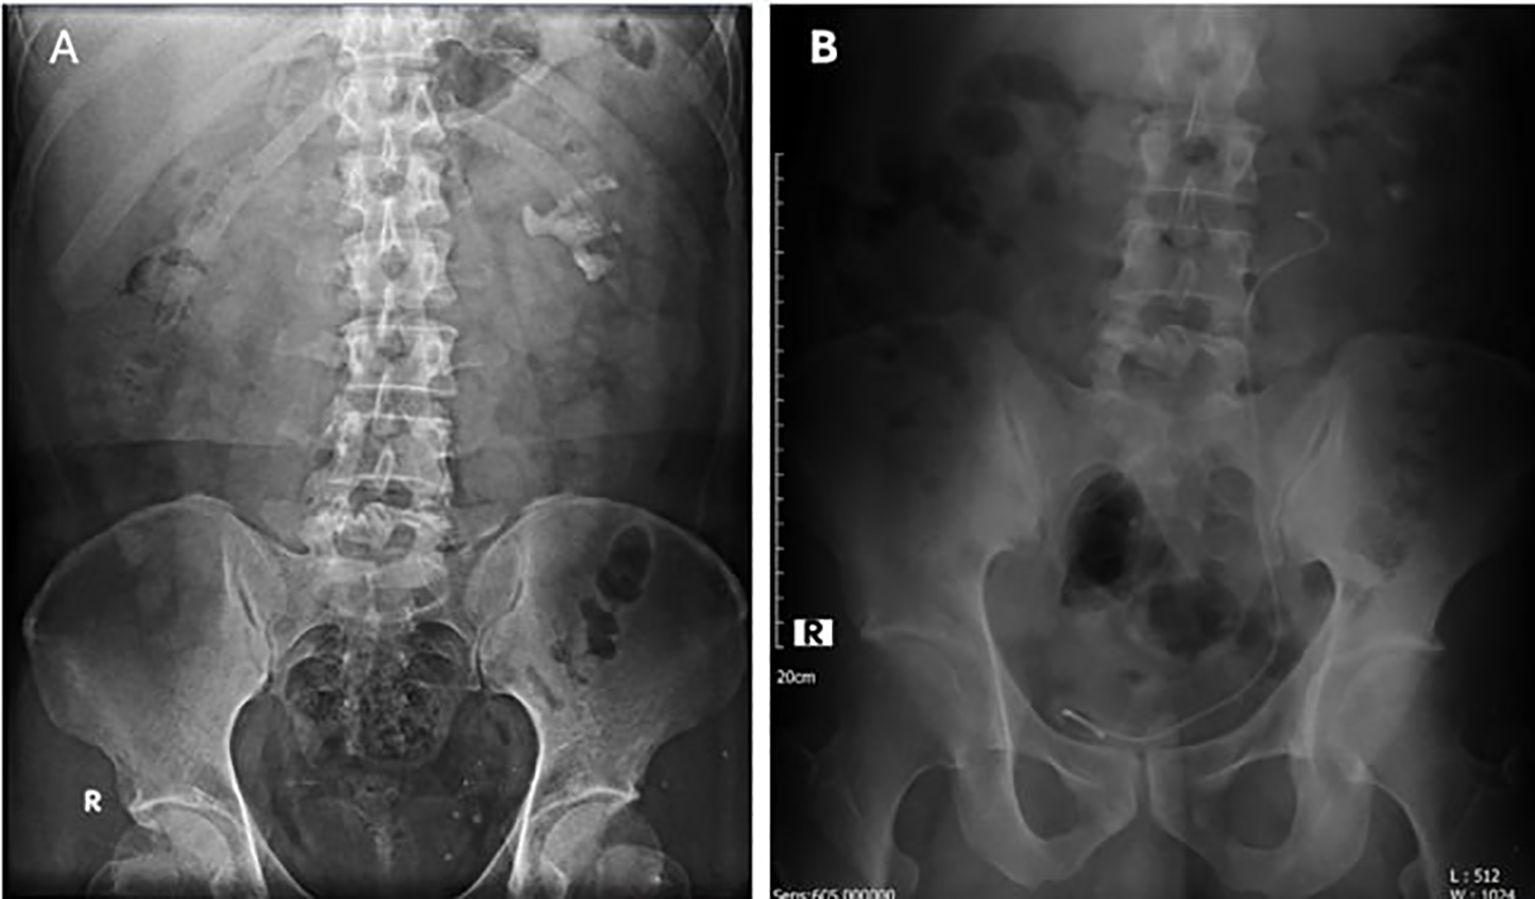

A 39-year-old male presented with colicky flank pain persisting for three weeks before entering hospital. His past medical history is reported to have dyslipidemia and gout. However, there is no past surgical procedure history. Patient confirm to experience a prior episode of spontaneous stone passage. Initial evaluation with urinalysis revealed microscopic hematuria (+1). Ultrasonography confirmed the presence of a large renal stone, prompting further diagnostic imaging. An X-ray (Figure 1A) and non-contrast computed tomography (CT) scan identified multiple left nephrolithiasis, including a staghorn stone measuring approximately 2.8 × 1.5 × 4.3 cm with a density of 1000–1200 Hounsfield Units (HU), occupying the mid-inferior pelvicalyceal system. Additional smaller stones (0.5–1 cm) were noted in the mid-inferior calyces. Associated findings included grade II hydronephrosis and left-sided hydroureter extending from the proximal to the distal ureter. A suspected ureterovesical junction (UVJ) stricture was also observed, likely secondary to the previous stone passage. No stones were identified in the ureter.

Figure 1. (A) Preoperative X-ray showing a staghorn stone in the left kidney; (B) Postoperative X-ray after RIRS with DISS, showing a DJ stent and a residual fragment (10 x 7 mm).

Postoperatively, the patient reported mild dysuria and reddish urine discoloration, which resolved within 24 hours. A Foley catheter was maintained for immediate postoperative management. Follow-up imaging with plain abdominal X-ray (Figure 1B) confirmed proper placement of the DJ stent, with the proximal tip at the L4-L5 vertebral level and the distal tip within the pelvic cavity. A single residual stone fragment measuring 10 × 7 mm was noted at the L3 vertebral level, resulting in a stone-free rate of 96.2%.